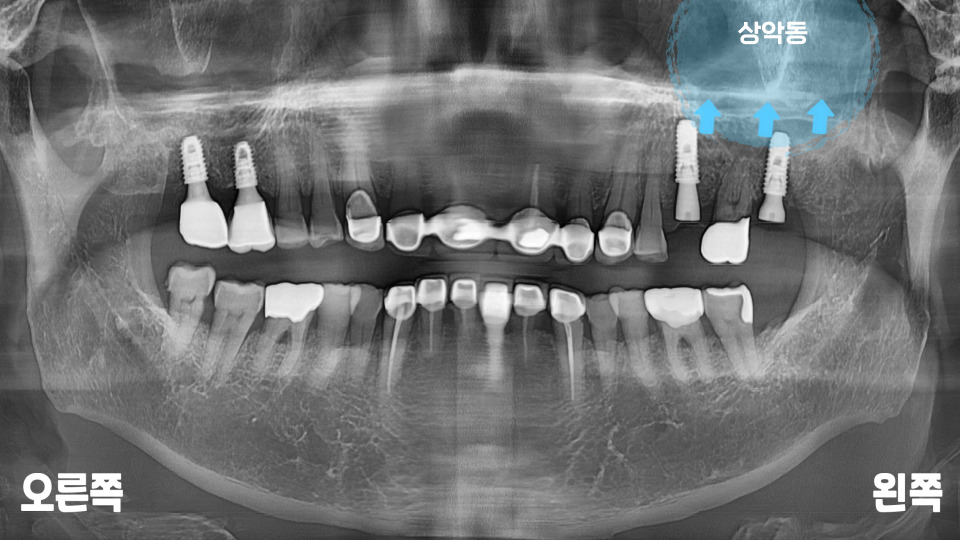

또한 파노라마로

전체적인 입 속 체크를

해 보았을 때,

왼쪽 맨 끝으로 아직

뼈가 덜 아문 흔적이 있습니다.

왼쪽 위 작은 어금니 주변으로

거뭇한 뿌리 끝 염증이

확인되는데요.

예전에 신경 치료했던

치아 속으로 탈이 난

모습입니다.

근단부 끝까지

제거 및 충전이

되지 않아 보여

재신경치료(re-endo)를

시도해 볼 수도 있겠지만,

심한 병소로 주변 뼈가

많이 녹아 있는 모습에

자연 치아를 살리기는

무리가 있어 보입니다.